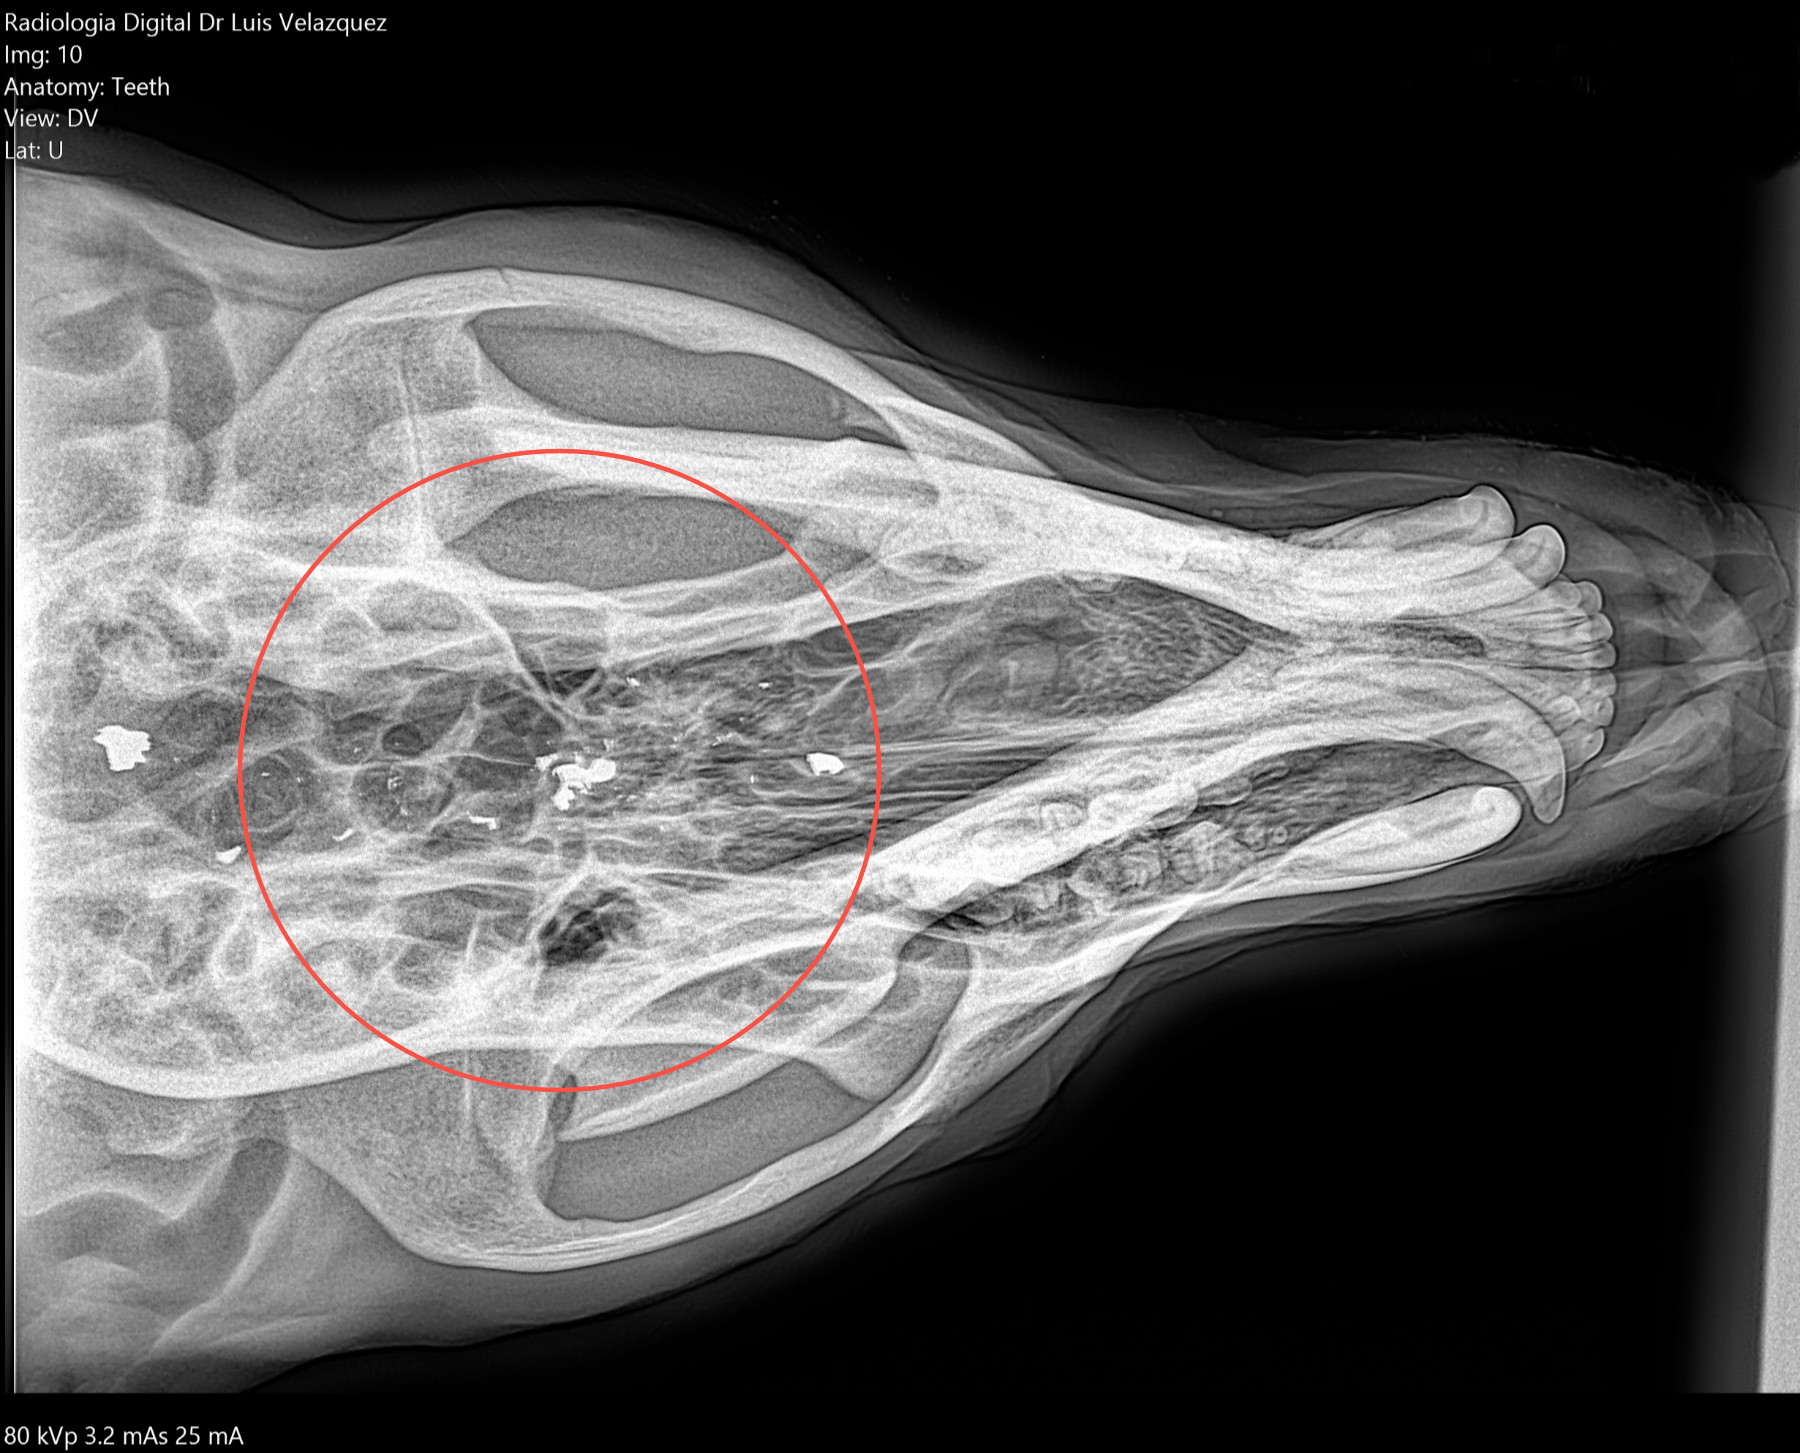

THE GENUS RHYNCHOTERIUM (MAMMALIA-PROBOSCIDEA) in the Hemphilliam - Blancan (NALMA) of central Mexico

In research in Neogene deposits from central Mexico, have collected abundant fossil materials, that have been referred to Rhynchotherium, based in not diagnostic materials and inaccurate age and locality, that not adequately di erentiate between the genus Rhynchotherium, Cuvieronius and Gomphotherium (Lucas y Morgan 2008).